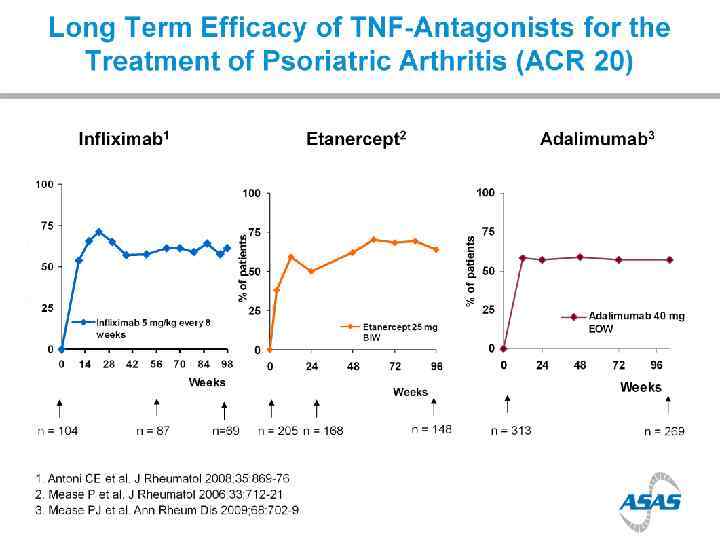

Efficacy of TNFi in AS

Treatment